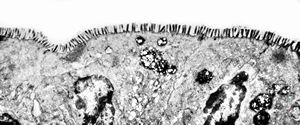

normal mucosa - jejunum - microvilli(anchored core rootlets)

normal mucosa - jejunum - microvilli